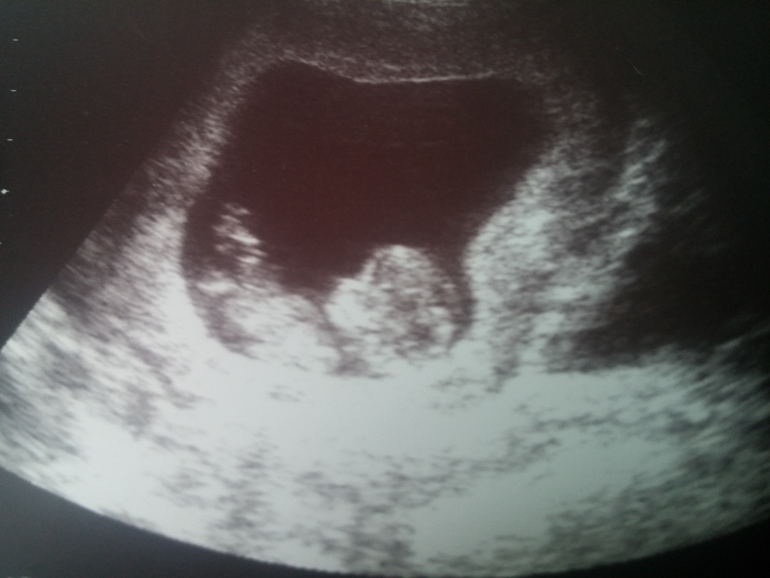

Результаты: УЗИ, КТГ, доплера, скринингаДумала напишу радостный пост по поводу вступления во второй тримест, но не тут то было. На 13 неделе мы в отличном здравии допроходили всех врачей для постановки на учет. Я уже думала вздохну свободно, но ввидимо не суждено. Сначала у нас в моче появился белок, а потом при перездаче и лейкоцити подскочили. Короче по анализам у меня начиналось восполение почек, а по ощущениям не было никаких симптомов. С этими анализами отправили нас в пренатальный центр на лечение. Где и выяснилось, что у меня безсимптомный пиелонефрит. Только в день поступления в роддом у меня начала наконец то болеть поясница. Я вот все не могу понять, как так ведь я реально берегла спину, так как знала, что у меня может вылезти эта гадость. Обидно! Ну ладно, это все вылечится. Теперь о хорошем😊 Мы на прошлой неделе были на узи. Нам все показали и маленькие пальчики и сердечко и попочку. А еще мы там ножками дрыкали. Счастья было, не передать.😊 Фотки скрининга прилагаю, вдруг кому то понадобится.